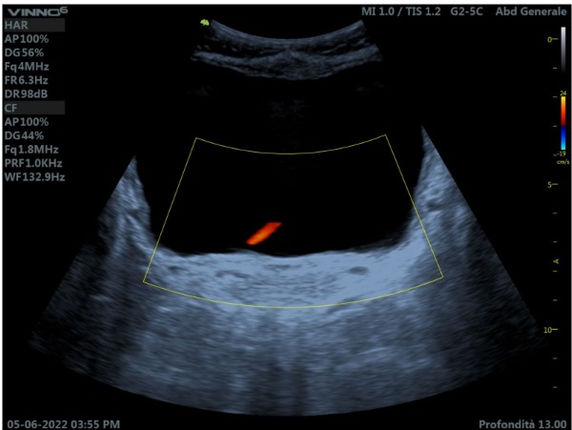

Moduli collo e vasi

Con un cambio di sonda e frequenza in queste lezioni esploreremo tutta la regione cervicale fino allo studio TSA.